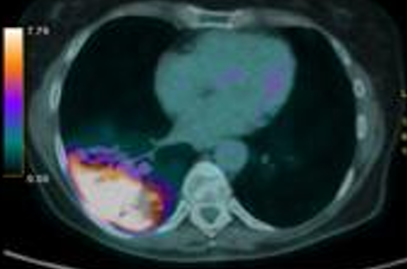

患者为66岁女性,ECOG体能状态评分为1分,有轻度吸烟史(5包年),合并2型糖尿病和银屑病。2023年6月,患者因持续干咳就诊,胸部CT显示右下肺叶有一7cm的肿块,伴有多发纵隔淋巴结肿大。进一步的FDG-PET检查显示右下肺病灶SUV值为13.6,双侧纵隔淋巴结SUV值为4.9,提示高代谢病灶。